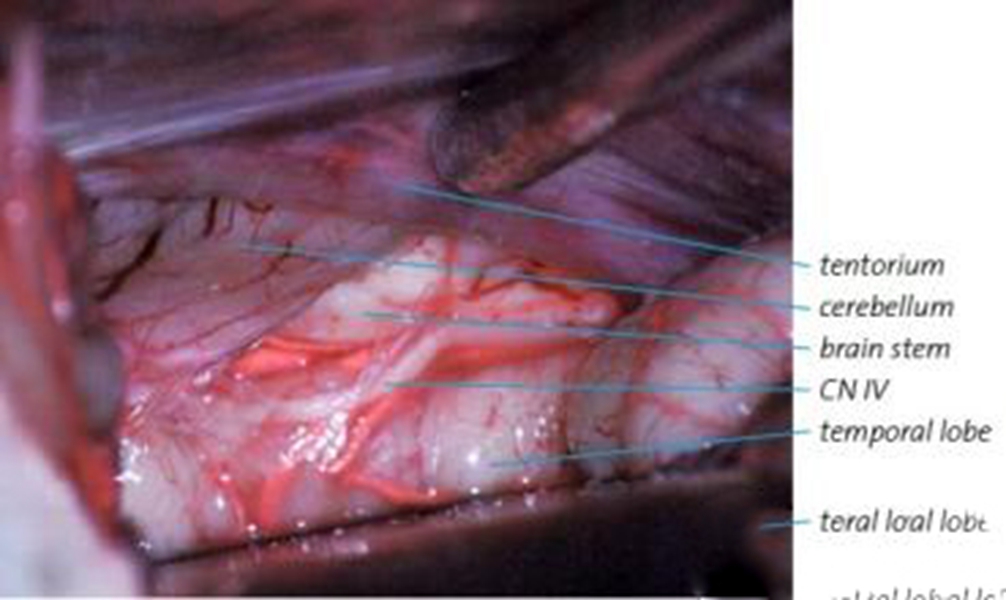

早期煙霧病

左側煙霧病